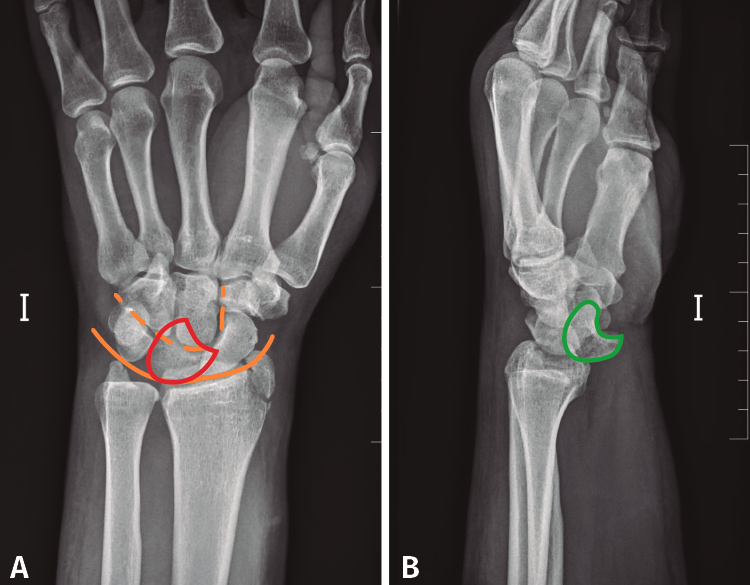

Se solicitó una radiografía anteroposterior y lateral pura de muñeca izquierda, en la que se observa una luxación transestiloperilunar (Figura 2).

Figura 2. A: radiografía anteroposterior en la que se observa la disrupción de los arcos de Gilula. Semilunar en flexión volar (rojo); B: radiografía lateral pura de muñeca en la que se observa la pérdida de la congruencia semilunar, hueso grande y 3.er metatarsiano (verde).